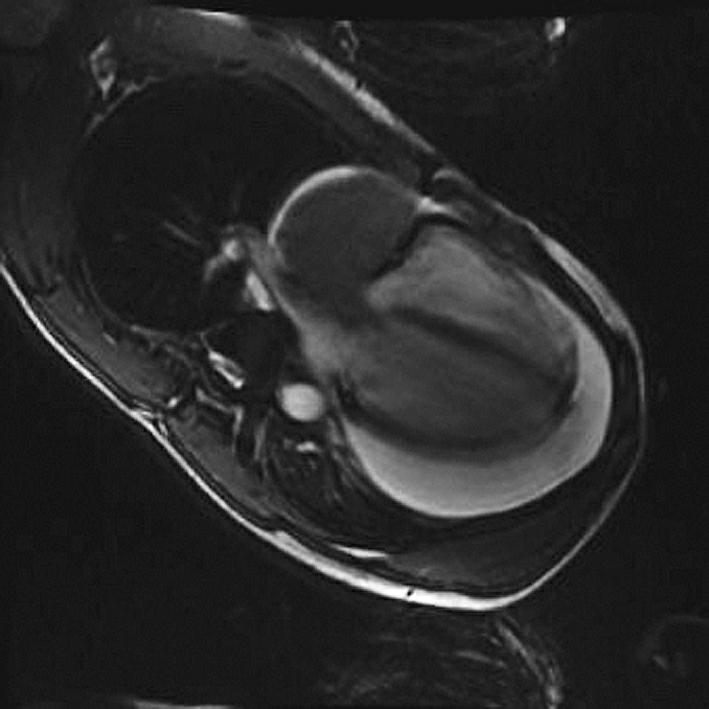

辅助检查:入院后行血常规、生化及结核与风湿免疫相关检验,均未见明显阳性结果,故考虑结核性心包积液可能性较小。后行心电图检查(2015年8月25日)示窦性心律,非特异性ST-T改变。X线胸片(2015年8月25日)示心影向双侧增大,呈烧瓶状。超声心动图(2015年9月1日)示舒张期心包腔内可见液性暗区:左室后壁21mm,右室前壁11mm,左室侧壁30mm,心尖20mm,右房顶10mm,剑突下20mm,心包腔内可见6.6cm×3.5cm实性团块,右室壁轻度受压(图1)。胸部增强CT(2015年8月26日)示心包腔内右心房上方见混杂密度肿块影,最大横截面积约6.1cm×4.0cm,病灶密度不均匀,伴有心包大量积液,少量右侧胸腔积液(图2)。心肌磁共振检查(2015年8月27日)示心包腔内团块状新生物,考虑恶性可能性大(图3)。随后在征得患者及其家属同意后,行PET-CT(2015年8月27日)检查,结果示心包腔内不均匀高代谢肿块,双侧颈根部及锁骨上窝多发高代谢肿大淋巴结,考虑恶性病变可能性大,伴随心包大量积液;右侧胸腔积液;腹、盆腔积液(图4)。综合以上检查及检验结果,考虑患者为恶性心包积液,心包腔内恶性病变可能性大,建议患者行穿刺活检,明确诊断。

图3心肌磁共振

随访结果:患者于肿瘤科接受化疗,经2个周期(每7天1个周期)后,再次行超声心动图检查,结果是肿瘤体积缩小,为5.7cm×3.4cm,同时未见明显心包积液(图6)。